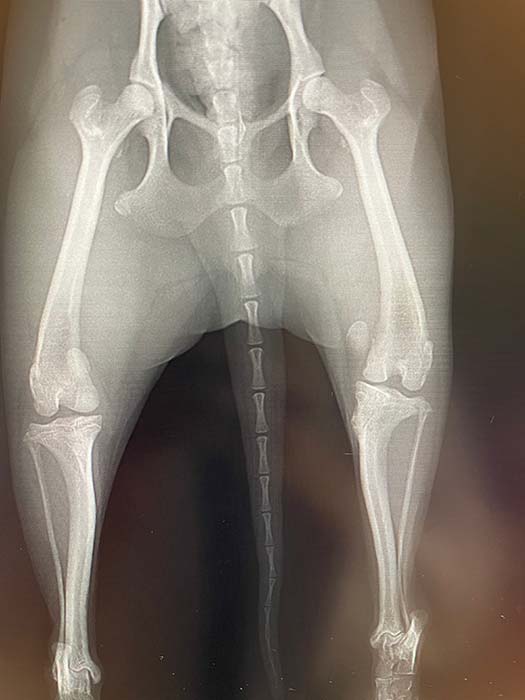

左後肢グレード4におけるレントゲン写真